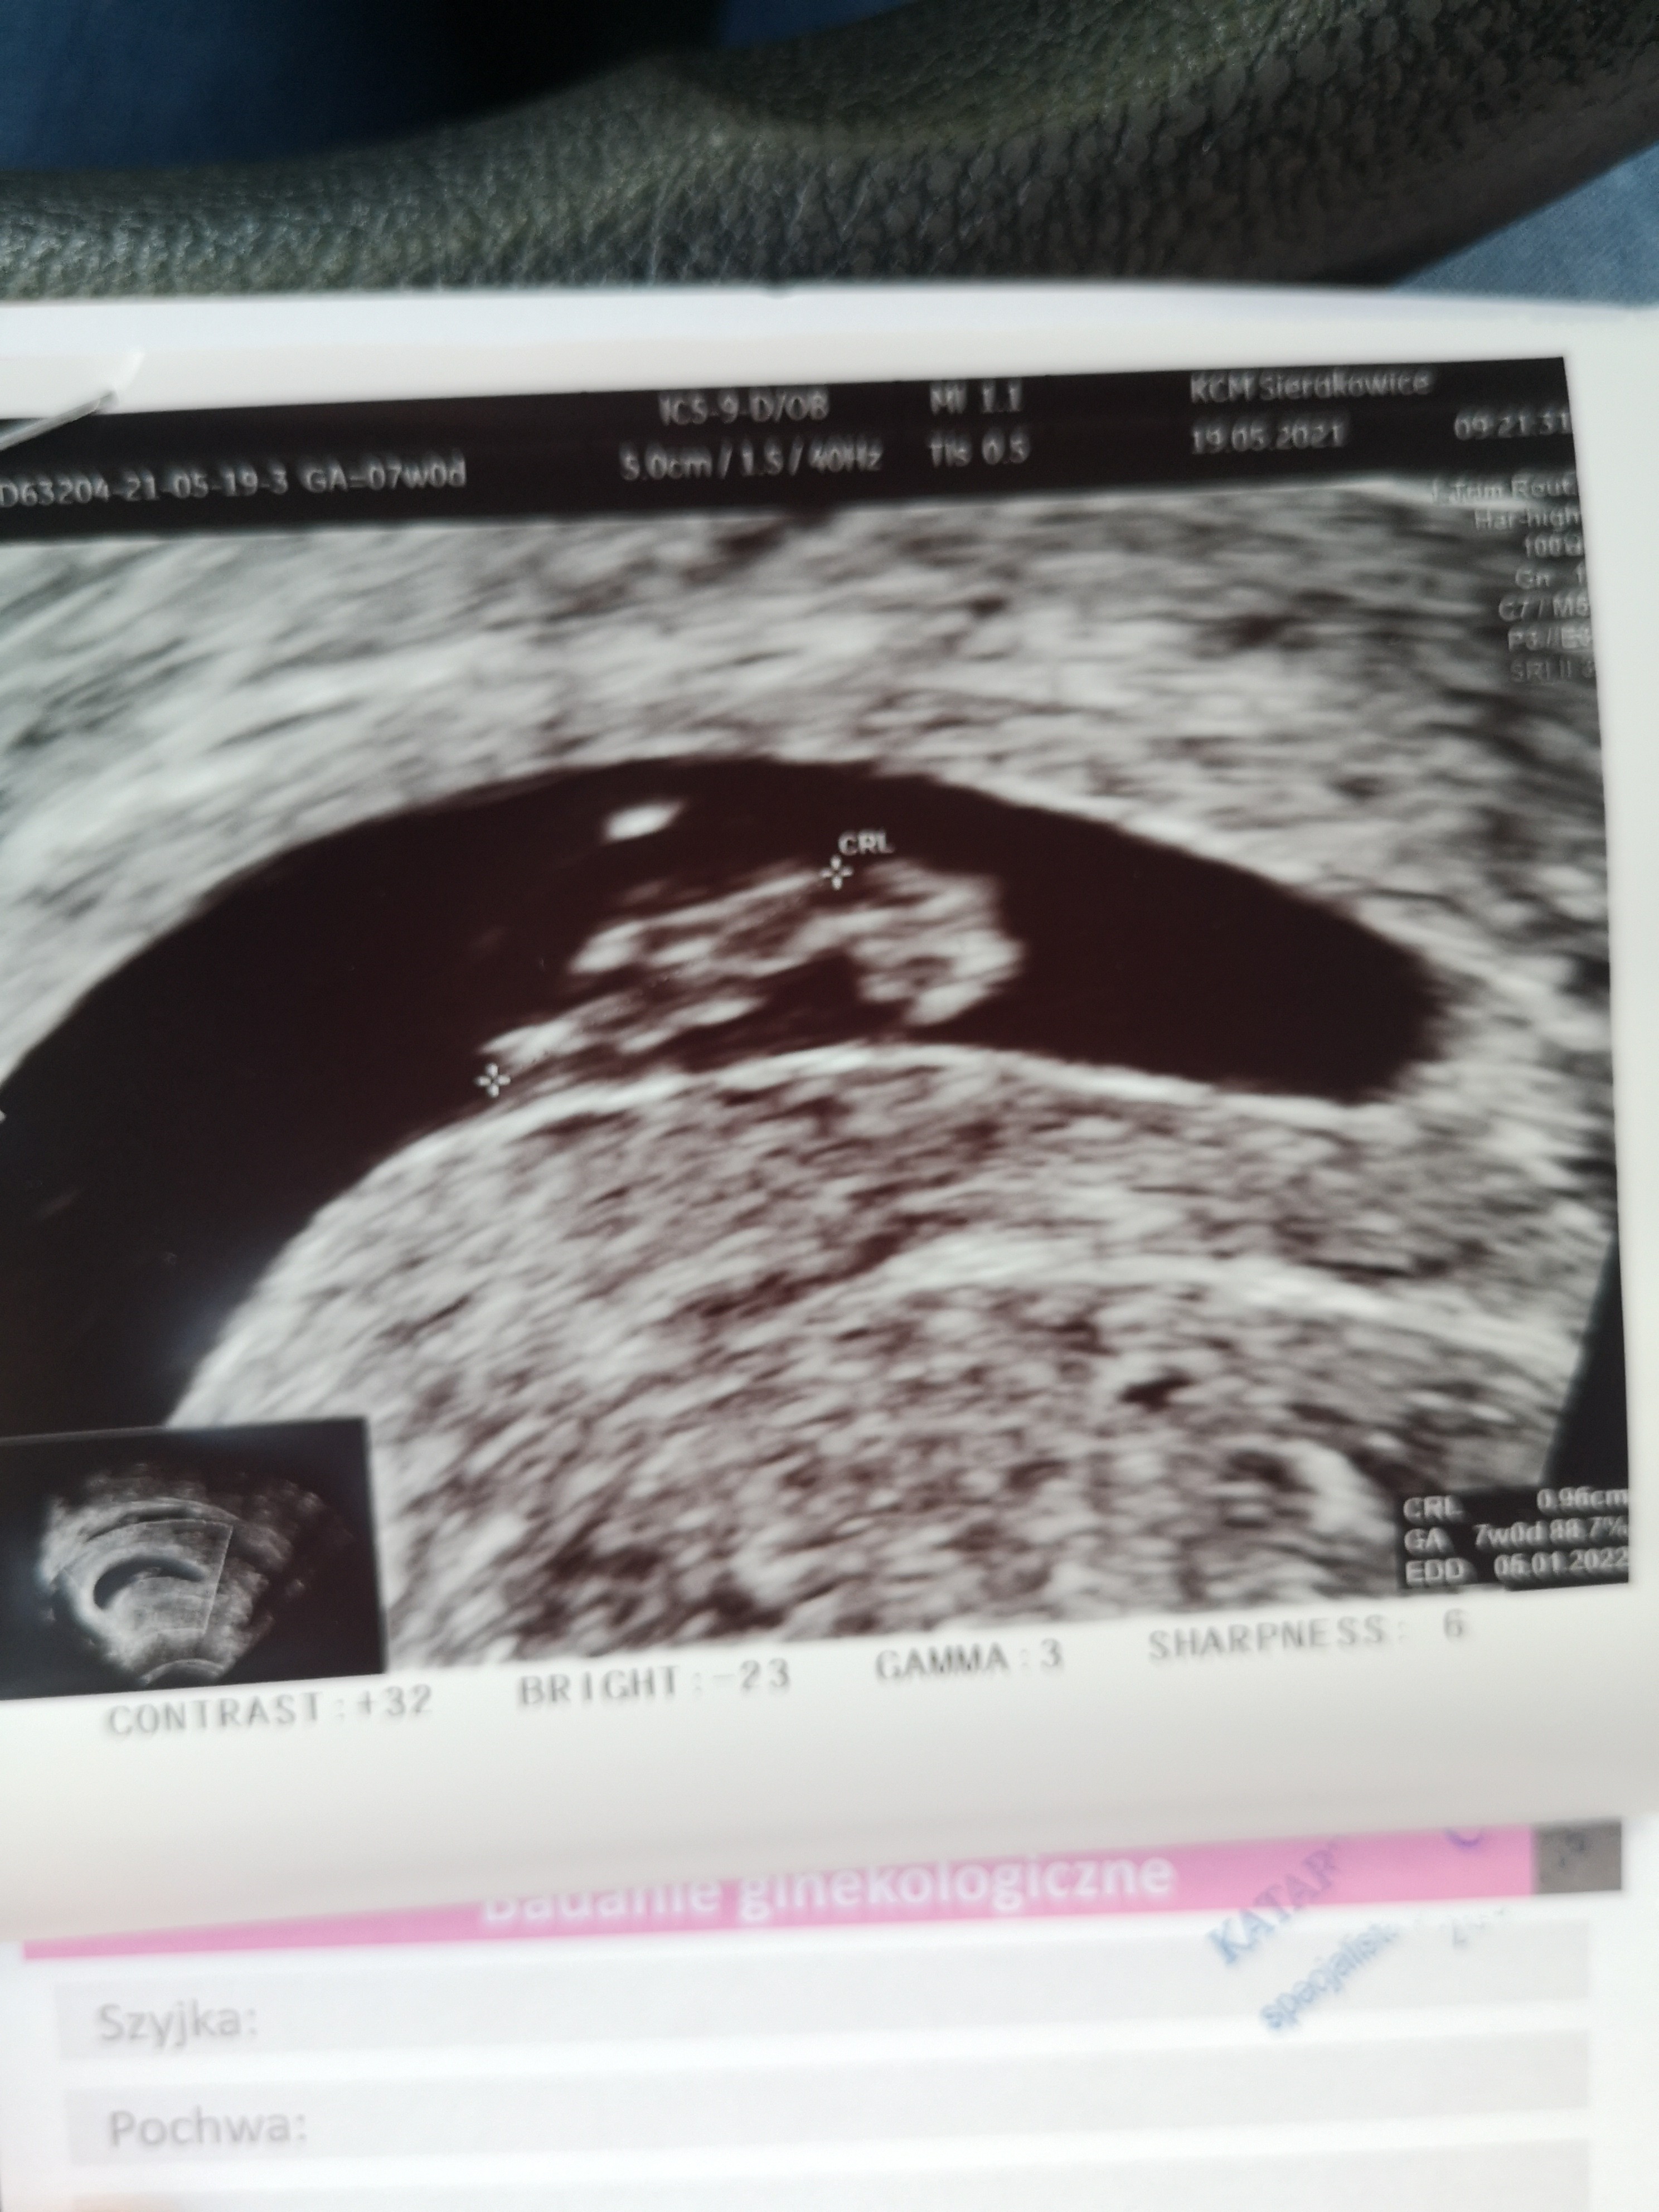

Wrzucam moje zdjęcie z 7+1. Zarodek 1cm, pęcherzyk ciążowy nie zmierzony, ale wygląda na ponad 3cm, także podobnie do tego u ciebie 😊 gdyby coś było nie tak, lekarz na pewno by powiedział :)